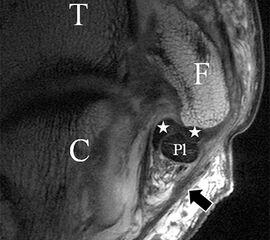

Der Ursprung des Ligamentum fibulocalcaneare liegt unmittelbar kaudal und dorsal des Ursprungs des Ligamentum fibulotalare anterius, so dass gehäuft kombinierte Verletzungen und auch ein gemeinsamer knöcherner Ausriss beobachtet werden. Nach kaudal dorsal verläuft das Band dann nach medial konvex unter die Peroneussehnen. Danach ist ein schräg deszendierender, gestreckter Verlauf bis zum calcanearen Ansatz abgrenzbar (Abb. 10). Dieser zu allen drei Standardebenen schräge Verlauf erschwert häufig die Diagnostik des LFC vor allem bei subtileren Verletzungen. Spezialprojektionen, die dem Bandverlauf orthograd folgen (entweder schräg coronar oder schräg sagittal) erleichtern auch hier die Diagnostik (Abb. 11) insbesondere nicht dislozierter Avulsionen. Assoziierte Verletzungen der Peroneussehnenloge müssen mit beurteilt werden, wobei neben Verletzungen der Sehnen und Sehnenscheiden die Beurteilung des Retinaculum peroneum superius und inferius wichtig ist. In einem Kollektiv von Patienten mit chronischen Außenbandinstabilitäten weisen 50% der Patienten eine Verletzung dieser Strukturen auf 5. Auch hier erleichtern hochauflösende Techniken die Diagnostik (Abb. 12).

Bezogen auf die Transversalebene verläuft die Syndesmose ca. 30° schräg cranio-caudal anguliert (Abb. 15 a). Häufig lassen sich drei Hauptfaszikel differenzieren: das kürzeste superiore, das stärkste mittlere und das längste kaudale Faserbündel. Ein akzessorisches Bündel, das anteriore-inferiore, tibiofibulare Ligament (AITFL) oder auch Bassett-Ligament wird in 80-94% der Patienten nachgewiesen 8. Dies weist einen unmittelbaren Bezug zur anterolateralen Talusschulter auf (Abb. 17). In Kombination mit einer Außenbandinstabilität und konsekutivem, talarem Vorschub kann dieses zu einem Impingement an der anterolateralen Taluskante führen mit nachfolgender chondraler oder osteochondraler Läsion.